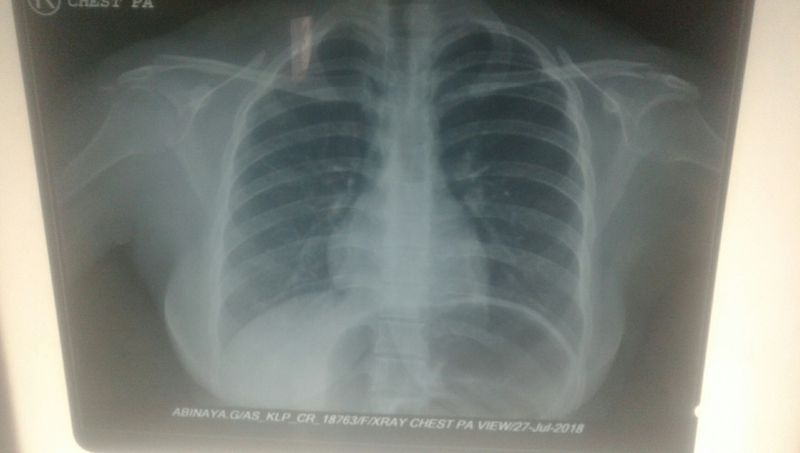

Chest x ray any asking interpretation

Ruptured diaphragm??